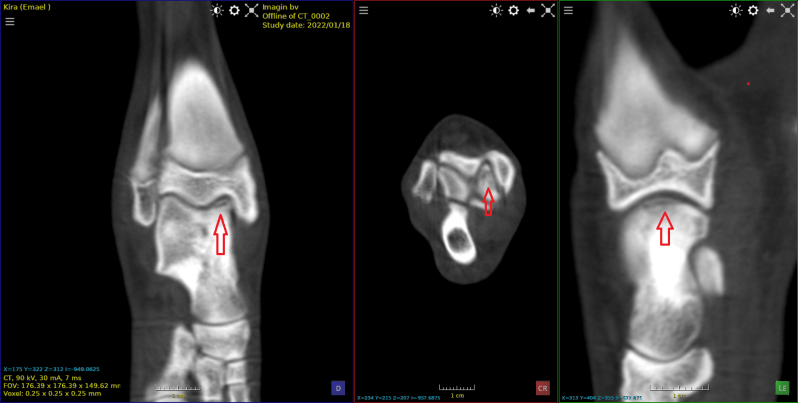

Deze Visla van 8 jaar werd aangeboden met een klacht van chronisch manken sinds 1 maand.

Op de scan is een  oud OCD - letsel zichtbaar met een gewrichtsmuis.

Het stukje werd operatief verwijderd.